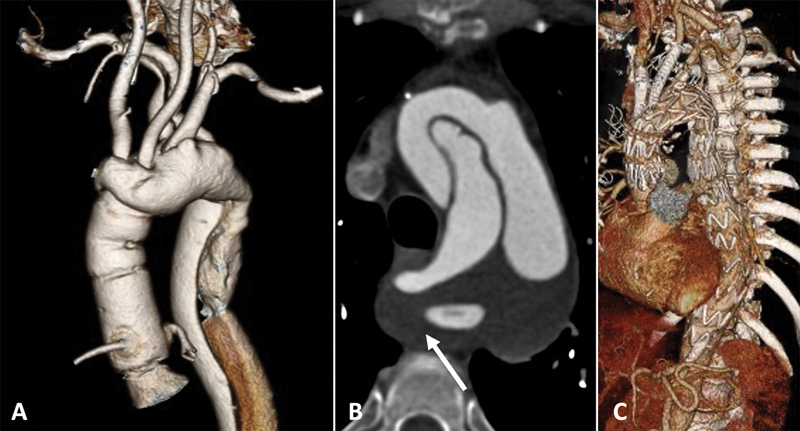

Abstract Image